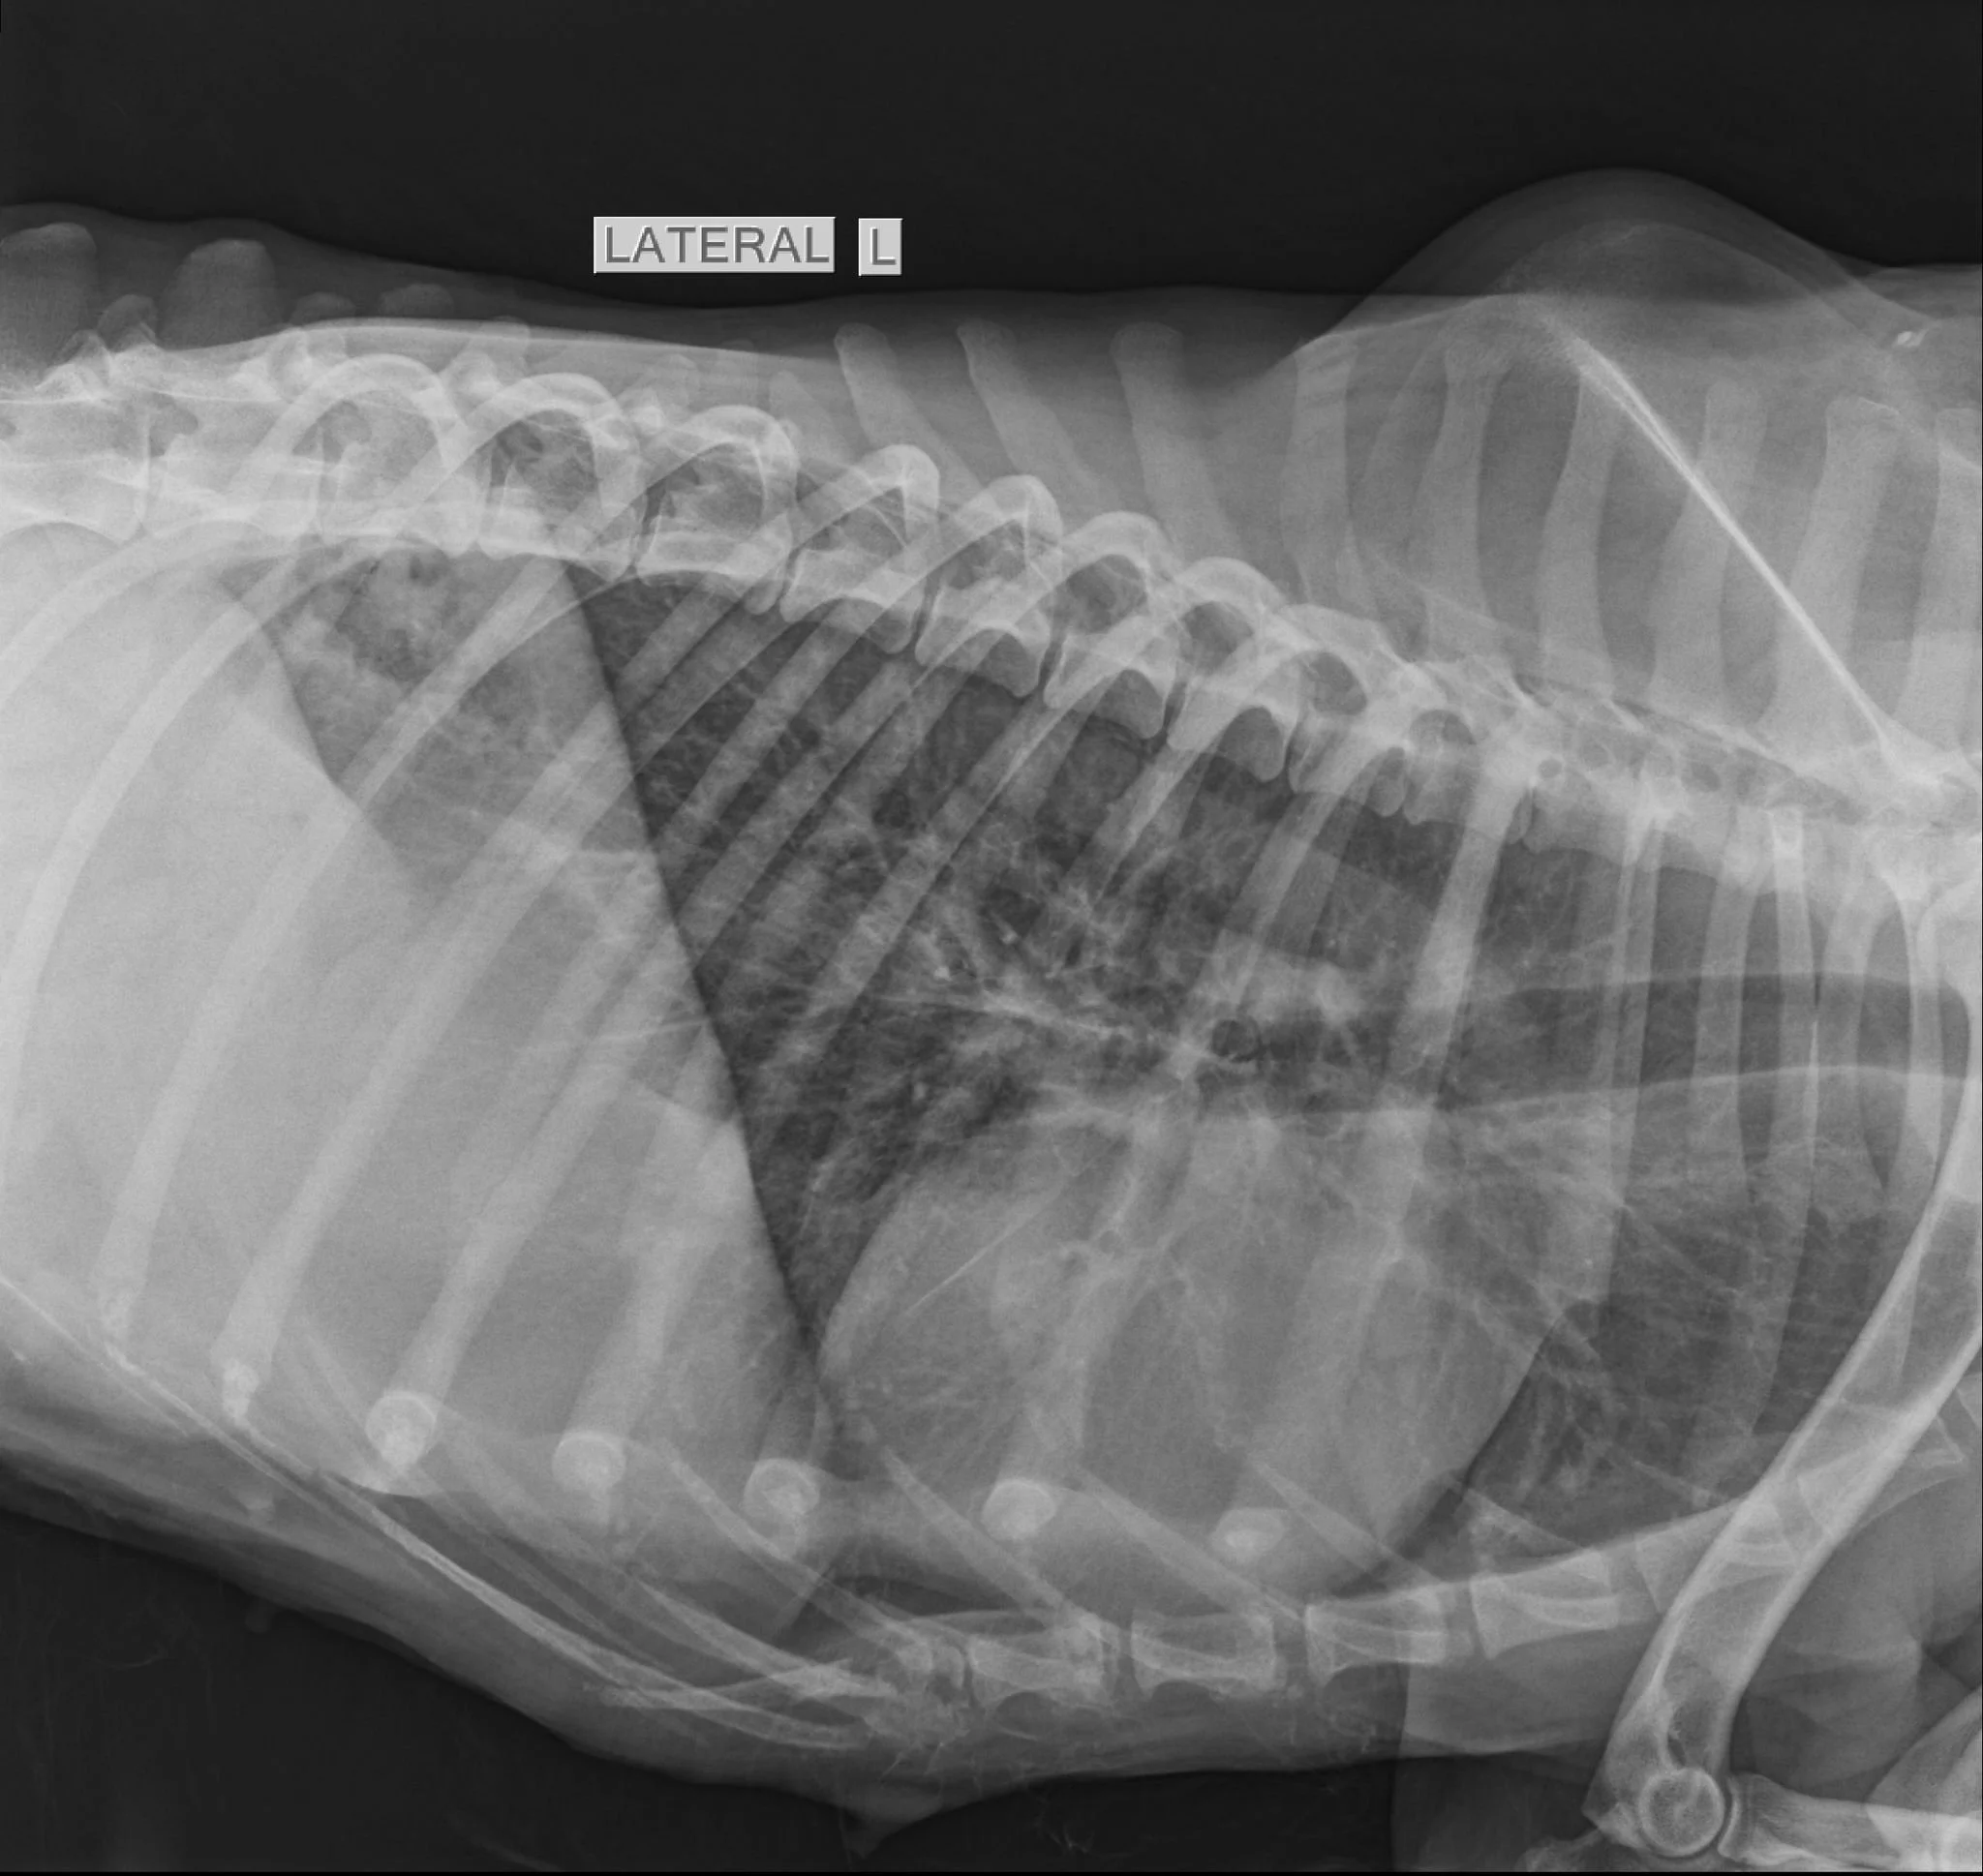

3.3. Afecțiuni toracice

Pentru afecțiunile toracice, radiografia permite evaluarea plămânilor și a inimii, fiind utilă în diagnosticarea bolilor pulmonare, a problemelor cardiace sau a prezenței lichidului în cavitatea toracică.